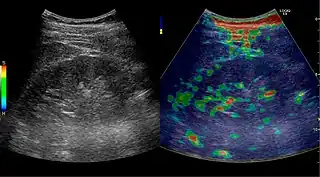

Elastography is a US method to visualize the elasticity of tissue. Preliminary reports on US elastography used on transplanted kidneys to evaluate cortical fibrosis have been published showing promising results (Figure 32).[1]

Figure 31. Unspecific cortical lesion on CT is confirmed cystic and benign with contrast-enhanced ultrasound (CEUS) using image fusion.[1] Figure 32. Strain elastography of a normal kidney. Red depicts soft areas, and blue depicts hard areas relative to the entire elastography image. Note that the medulla is softer than the cortex. A color bar is shown to the left of the image, where "S" and "H" denote soft and hard tissue, respectively.[1]

Figure 32. Strain elastography of a normal kidney. Red depicts soft areas, and blue depicts hard areas relative to the entire elastography image. Note that the medulla is softer than the cortex. A color bar is shown to the left of the image, where "S" and "H" denote soft and hard tissue, respectively.[1]